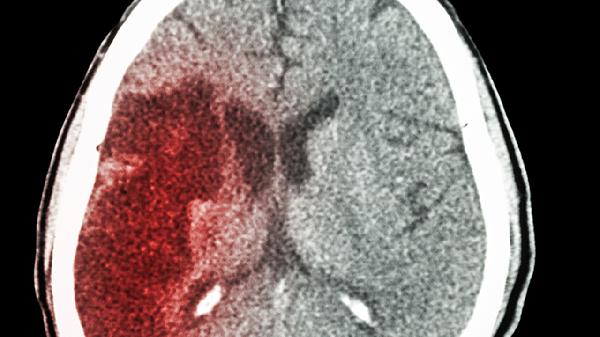

当出血范围广泛或损伤颞叶内侧结构时,记忆功能恢复往往受限。弥漫性轴索损伤会导致神经网络连接中断,使情节记忆提取困难。合并脑积水或继发癫痫可能进一步加重认知损害。此类情况需联合神经保护剂如依达拉奉注射液、脑蛋白水解物注射液等药物延缓进展。经颅磁刺激等物理治疗对部分难治性病例可能有一定效果。长期认知障碍患者需在专业机构进行生活能力评估,必要时采取监护措施防止意外事件发生。